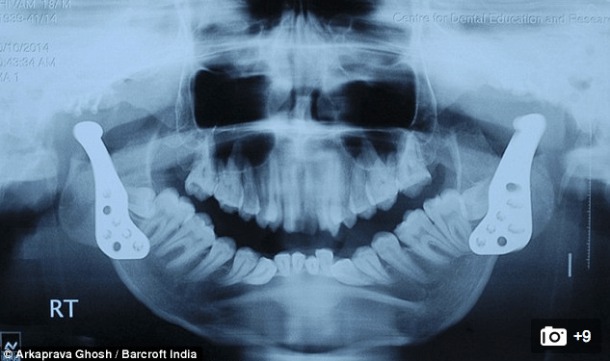

Mais voilà que deux médecins ont réussi à lui reconstruire une mâchoire, faite de joints artificiels. Si pour le moment, Shivam continue de s’alimenter sous forme liquide, il réussit enfin à ouvrir la bouche, chose qui était impossible jusqu’à présent. On suppose que de longs mois (années ?) de rééducation seront nécessaires pour lui permettre de reprendre un train de vie un tant soit peu normal, mais on ne peut que saluer cette nouvelle prouesse médicale.